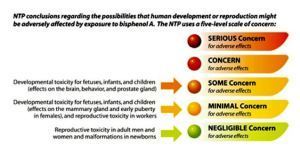

How to Avoid BPA

Great info in the articles and their infographics for the sections, below, about what steps we can take right now and in the future to remove BPA from our lives.

image from http://desdaughter.wordpress.com/2014/04/16/how-to-avoid-bpa/